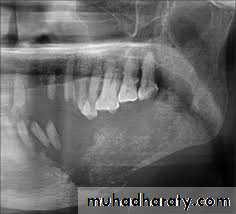

Radiographical appearance ;

It is possible to see a patient with acute osteomyelitis that has a normal-appearing orthopantomogram. However, one can often see the appearance of "moth-eaten" bone or sequestrum of bone, which is the classic appearance of osteomyelitis.14

Computerized tomography (CT) scans have become the standard in evaluating maxillofacial pathology such as osteomyelitis. its sensitive in late stage when 30%-50% of the bone demineralized.

The clinical picture of ORN is most commonly seen with pain and exposed bone in the maxillofacial region ORN is more common in the mandible than in the maxilla . A dosage of radiation above 5,000 to 6,000 rads is generally felt to make the mandible susceptible to ORN. Radiographically, the appearance on the orthopantomogram or CT scan resembles conventional osteomyelitis with areas of osteolysis and bony sequestrum. Often there is an appearance of moth-eaten bone present on these films: treatment of ORN is aimed at removing the nonviable (necrotic) tissue and allowing the body to heal itself. Minor debridements of exposed bone and Current therapy of HBO consists of 100% oxygen delivered in a pressurized manner.